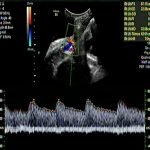

At 35 weeks of gestation, Doppler study showed absent end diastolic velocity in the umbilical artery and EFW 0 centile with normal liquor. The Ductus Venosus was explored and the PI was 99th centile. The clinico-demographic and Doppler parameters were assessed using the Barcelona algorithm available online and the fetus was determine to have progressed to Stage 3 FGR with early acidemia.